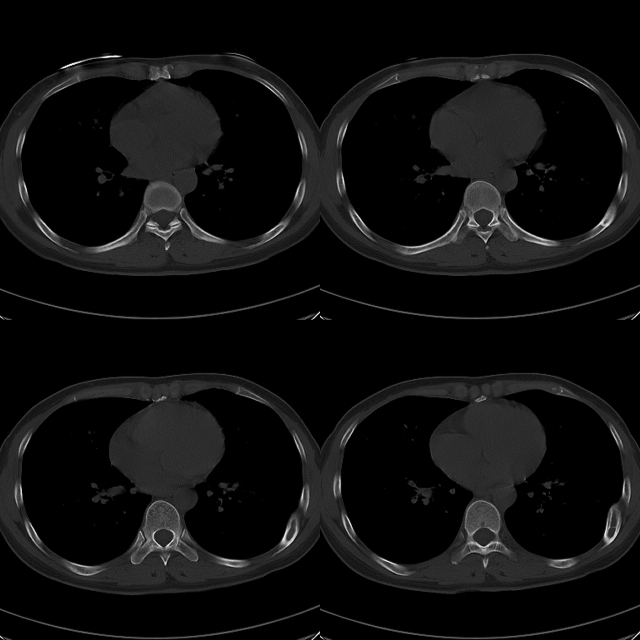

标题: CT19623:F40y,肋骨改变。

40岁女性,双侧胸部疼痛,以左侧为明显1+年。余无明显异常。

左侧肋骨骨纤维异常增殖症,

骨囊肿?

左侧肋骨单发膨胀性病变,皮质连续,病史较长,首先考虑良性病变:骨纤可能性大。